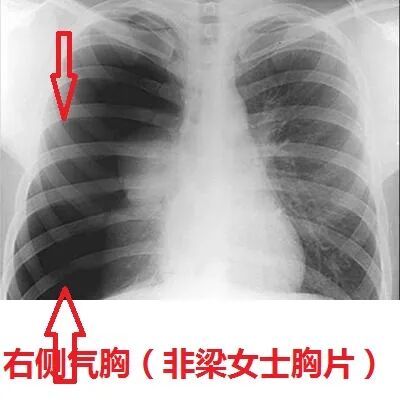

梁女士的左侧肺脏几乎是黑乎乎一片了,没有看到任何肺组织纹理了。这就是气胸了啊!

左侧气胸!

胸片看到的跟急诊科医生听诊器听到的是符合的,医生听到梁女士左侧呼吸音是几乎没有的,而现在胸片也看到左侧没有肺纹理,肺脏被压缩了,那就100%是气胸了。

梁女士现在仅仅靠着右侧一个肺在苦苦支撑着,所以为什么会有缺氧,为什么会有胸闷、心慌,就是因为这个气胸。